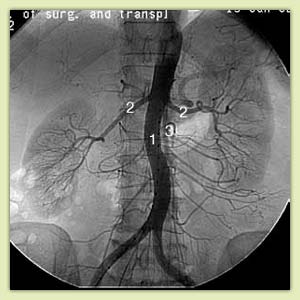

Примеры ангиограмм:

|

Опухоль правого надпочечника (1), отдавливающая сосуды кишечника (2) и печени (3) |

Аортография.

Контрастируются аорта (1), артерии почек (2), кишечника (3)